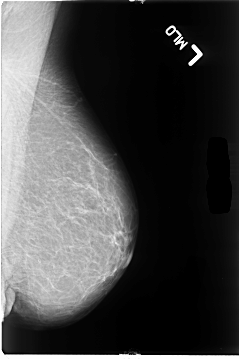

B_3055_1.LEFT_MLO

LEFT_MLO LINES 4664 PIXELS_PER_LINE 3096 BITS_PER_PIXEL 12 RESOLUTION 50 NON_OVERLAY